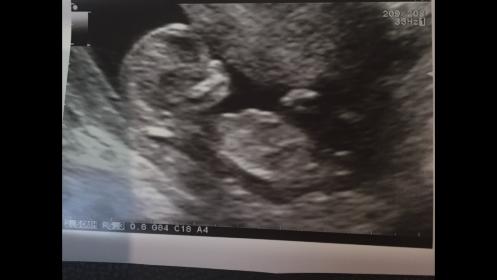

I am new here & was wondering if you would all like to give my baby's gender a guess! The scan photos attached were done at 12 weeks 3 days. The arrows are pointing to what we believe is the nub.